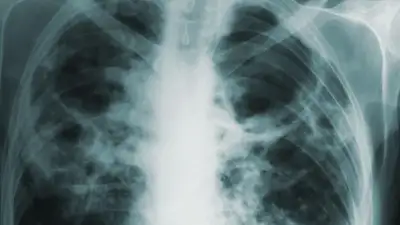

Легионеллез ("болезнь легионеров") – бактериальная инфекция, приводящая к опасной форме пневмонии, а также к отказу жизненно необходимых органов в самых тяжелых случаях. Чаще всего бактерия легионелла встречается в резервуарах и механизмах, которые используют воду, но не обслуживаются должным образом. К таким системам могут относиться бассейны, фонтаны и увлажнители воздуха. При этом бактерия может передаваться как от непосредственного контакта с неочищенной водой, так и через вдыхание пара.